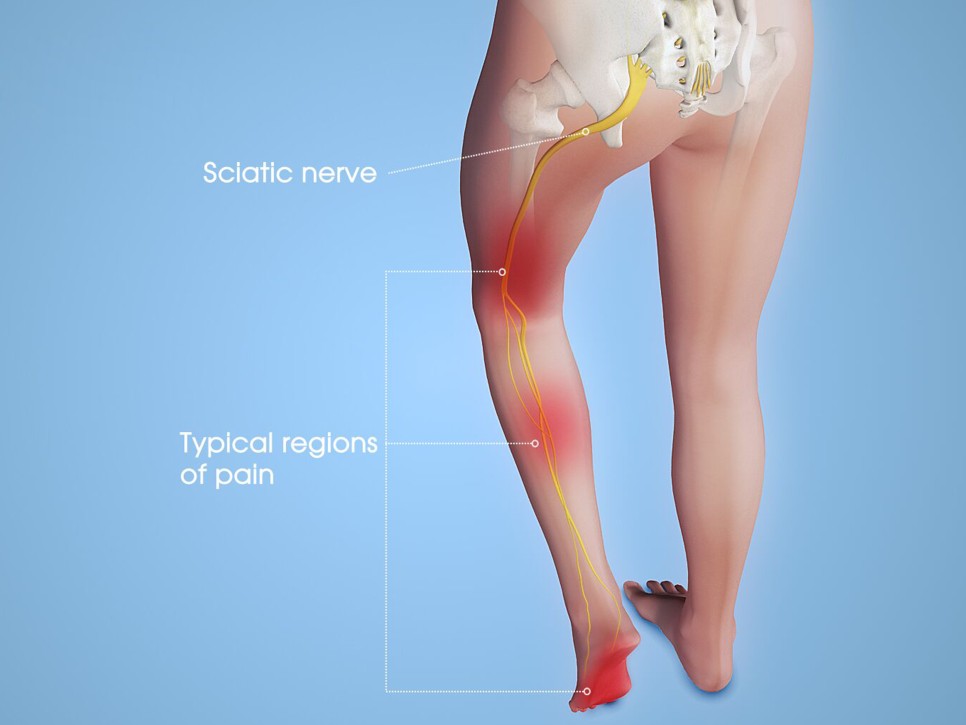

좌골을 지나 다리로 이어지는 좌골신경은 엉덩이 및 허벅지 바깥쪽에서 시작하여 종아리 바깥쪽/뒤에 띠 모양으로 이어지는 통증이 일반적입니다.

- 날카로운 통증-저리고 아프거나 전기가 오는 듯한 따끔따끔한 통증-칼에 저리는 느낌 등 환자의 표현에 따라 다양하게 나타난다-통증이 지속되거나 단속적으로 나타날 수 있다.- 배변, 기침, 무거운 물건을 들었을 때처럼 복압이 증가할 때 통증이 유발 – 감각 둔화, 다리에 힘이 빠지는 증상